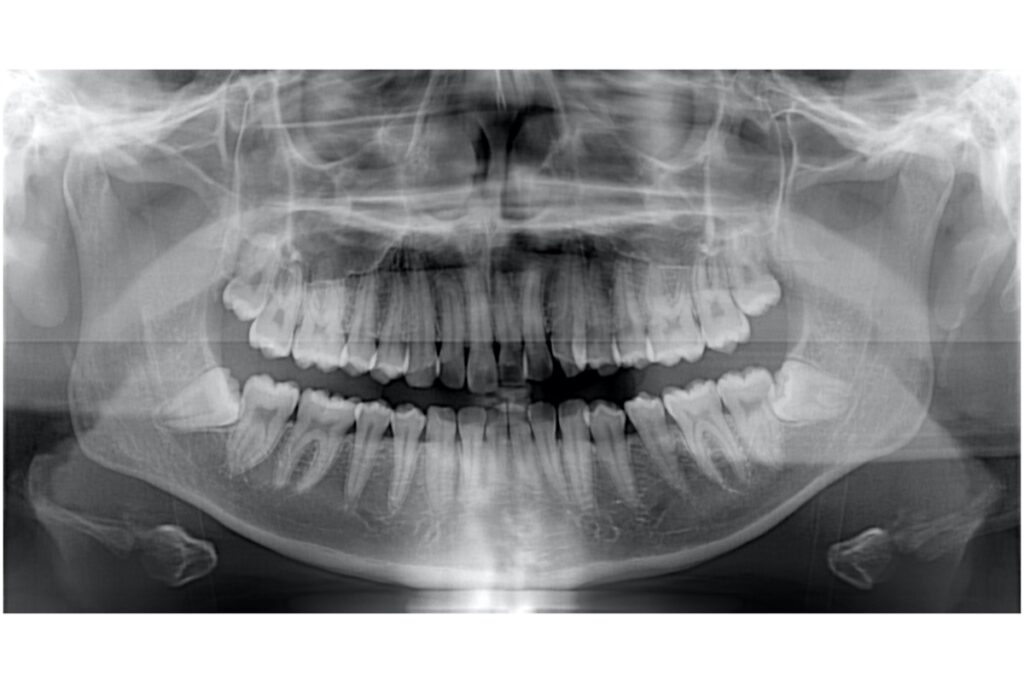

• レントゲン撮影(セファロ・パノラマなど)